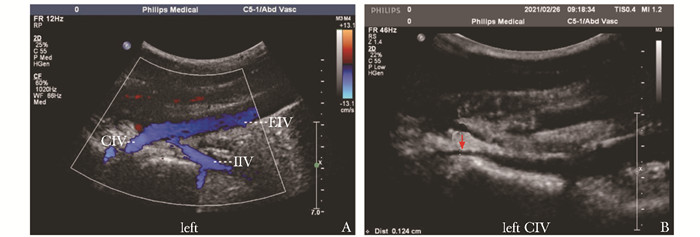

• 摘要: 胡桃夹综合征是一种罕见疾病,可导致患者出现蛋白尿、肾功能受损及生殖静脉曲张等系列症状。传统开放手术方式首选左肾静脉转位术,但手术创伤较大,术后近、远期并发症较多,影响患者生活质量。本文报道1例胡桃夹综合征合并左精索静脉曲张的男性青年患者,采用左生殖静脉-下腔静脉转流术并左精索静脉高位结扎术的手术方式,取得了良好治疗效果。该手术方式为胡桃夹综合征合并精索静脉曲张患者提供了新的治疗思路,值得临床借鉴。

Abstract: Nutcracker syndrome (NCS) is a rare disease that may cause proteinuria, renal dysfunction and varicose of genital veins. Traditional open surgery prefers left renal vein transposition, but this surgical method is more traumatic and patients often have more postoperative short-term and long-term complications affecting the quality of life. This article reports a case of a young male patient with NCS complicated with left varicocele. He was treated with left gonadal vein-inferior vena cava transposition and high ligation of spermatic vein, which achieved good results after surgery. This surgical method provides a new treatment idea for patients with NCS and varicocele, which is worthy of clinical reference.